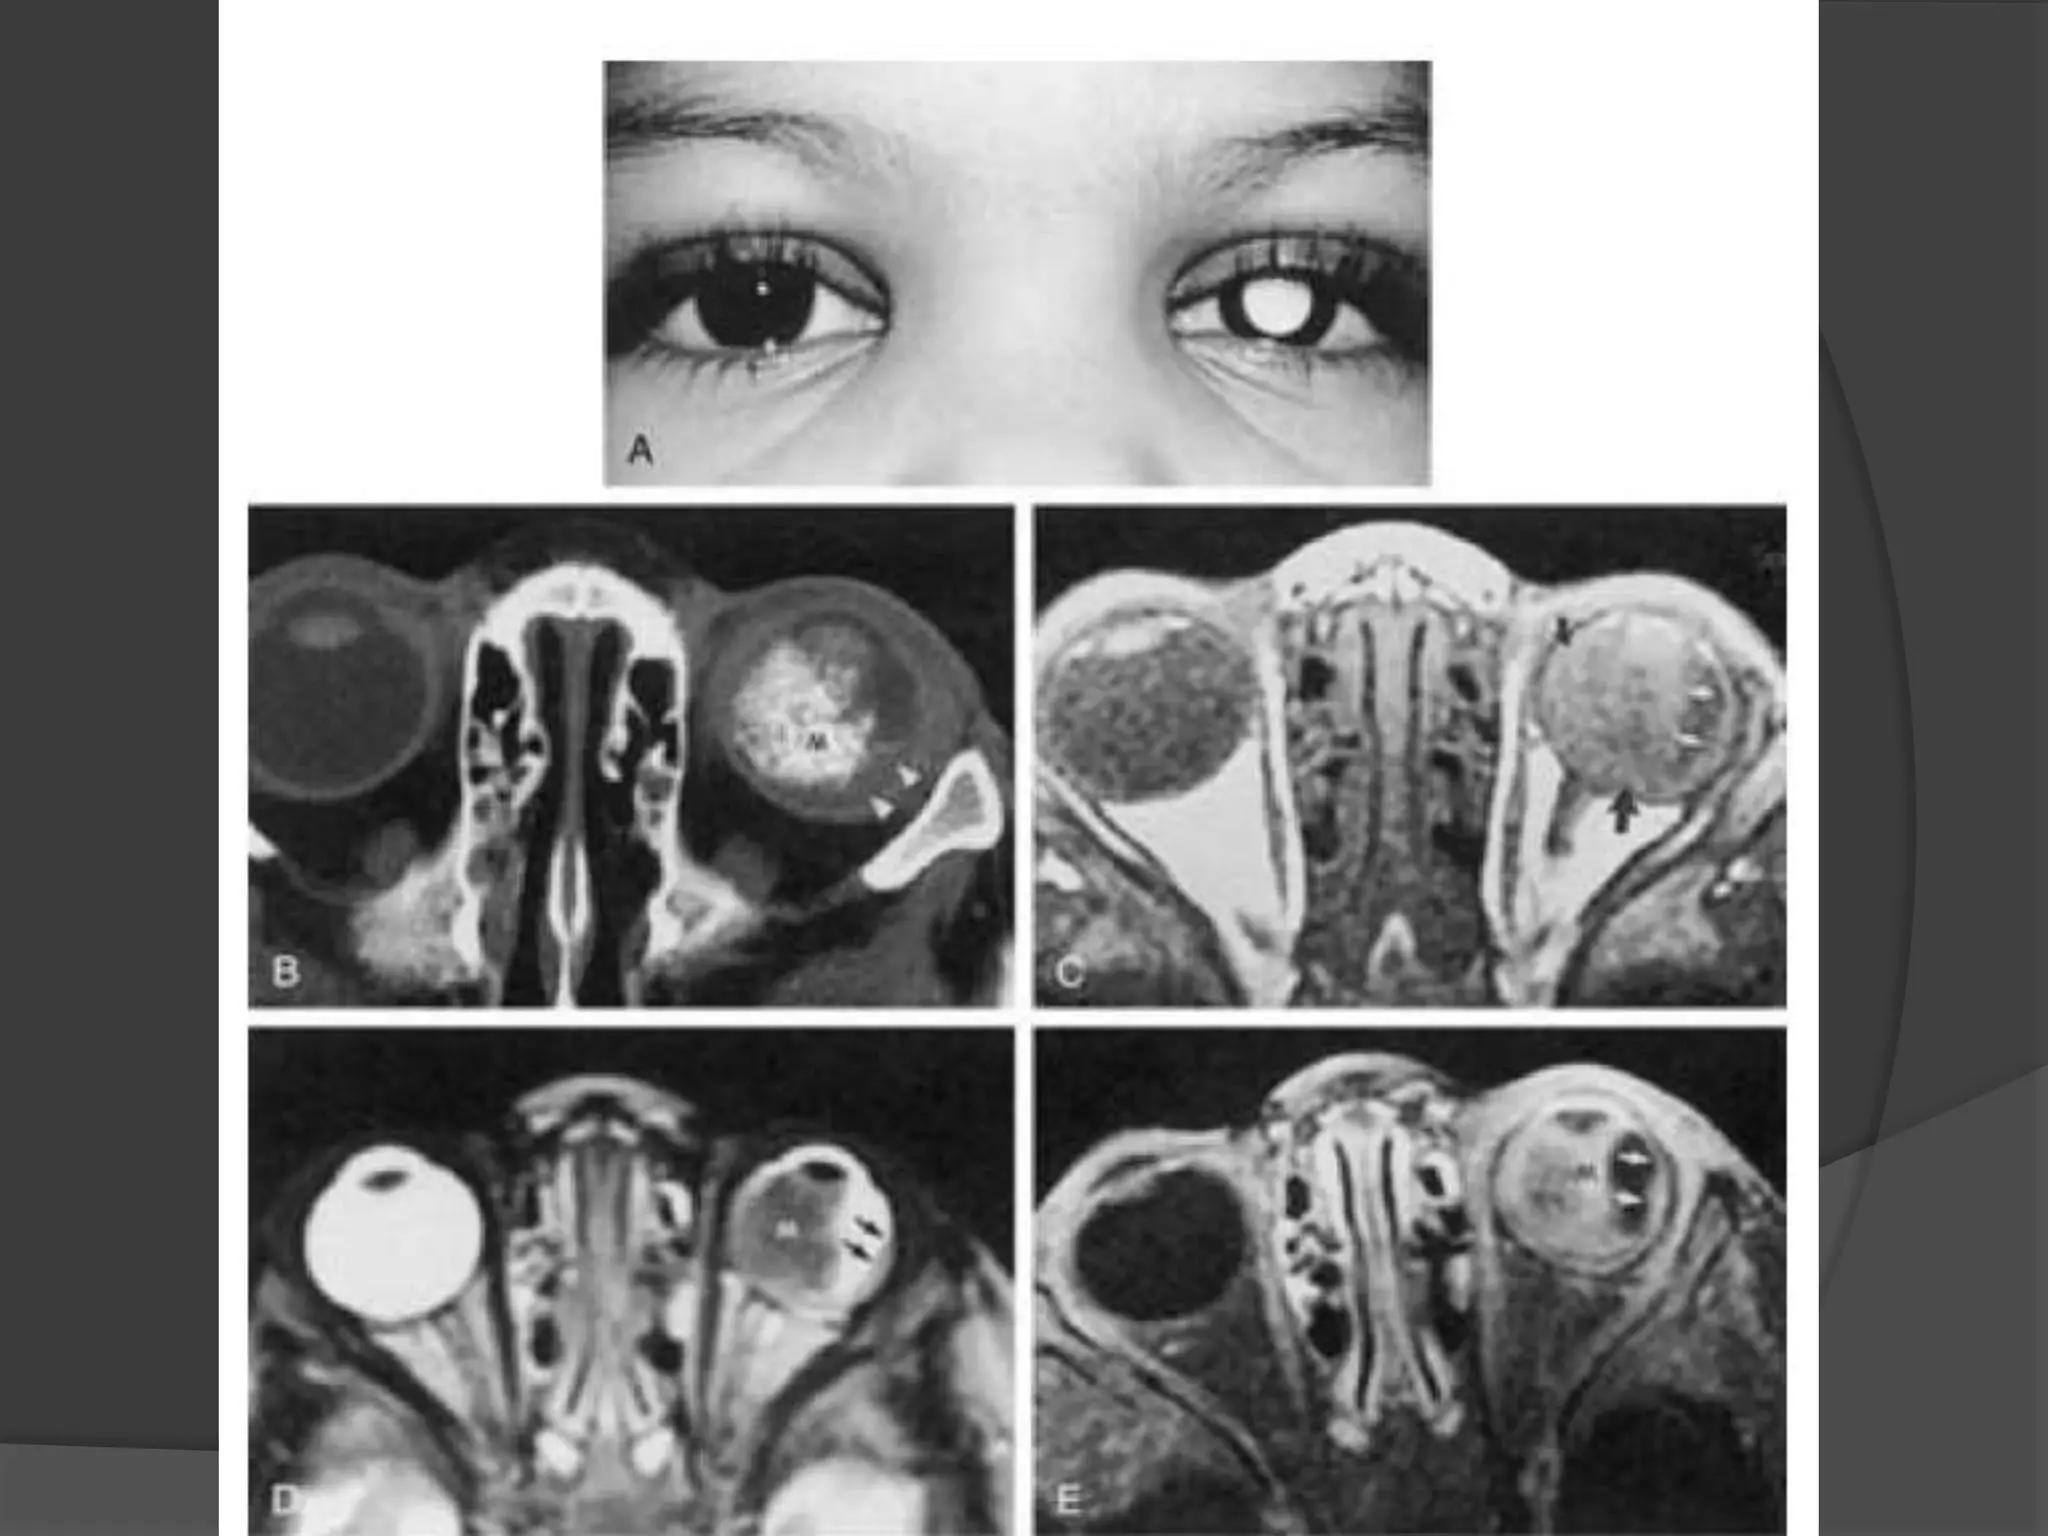

• #26 Retinoblastoma. A, Leukokoric left eye (whitish papillary reflex). B, Axial CT scan shows a large calcified intraocular mass (M). Note the noncalcified component (arrowhead). C, Axial T1WI shows a relatively hyperintense infiltrative mass (arrows). D, Axial T2WI shows a hypointense infiltrative mass (M). Note the extension along the temporal aspect of the globe (arrows).

• #27 Retinoblastoma with optic nerve involvement. A, Enhanced, fat-suppressed, axial T1-weighted MR image shows marked enhancement of a retinoblastoma (R) with extension into the optic nerve (arrow). B, Photomicrograph of an enucleated eye showing the tumor (T) as well as extension into the optic nerve head (arrow). (Courtesy of D. Ainbinder, MD, Tacoma, WA.)

• #33 Coats’ disease. A, Axial CT scan shows generalized increased density of the left globe caused by bullous retinal detachment. The leaves of the detached retina are faintly seen, as shown by the arrows. B, Axial PW MR image shows hyperintensity of the left globe caused by subretinal lipoproteinaceous effusion. Note the leaves of the detached retina (arrows). C, Axial T2-weighted MR image shows the detached retina (arrows).